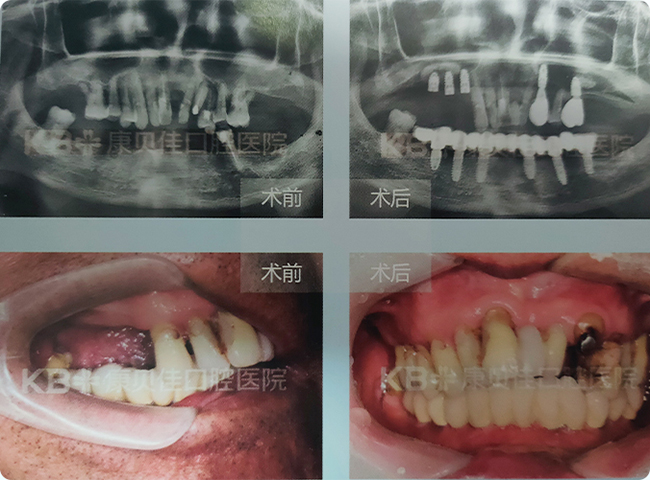

顾先生 79岁

患者下半口缺牙长达20多年,由于下颌双侧后磨牙都已缺失,咀嚼力丧失严重,平时只能吃些流食。身体状况很差。说话、社交都受到很大的影响。 后来找到艾斯纳博士,通过下颌种植6颗,恢复12颗功能牙的"缺多种少"方案,帮助患者重拾自信咀嚼力。

治疗方案:

上颌种植5颗 下颌种植6颗恢复半口